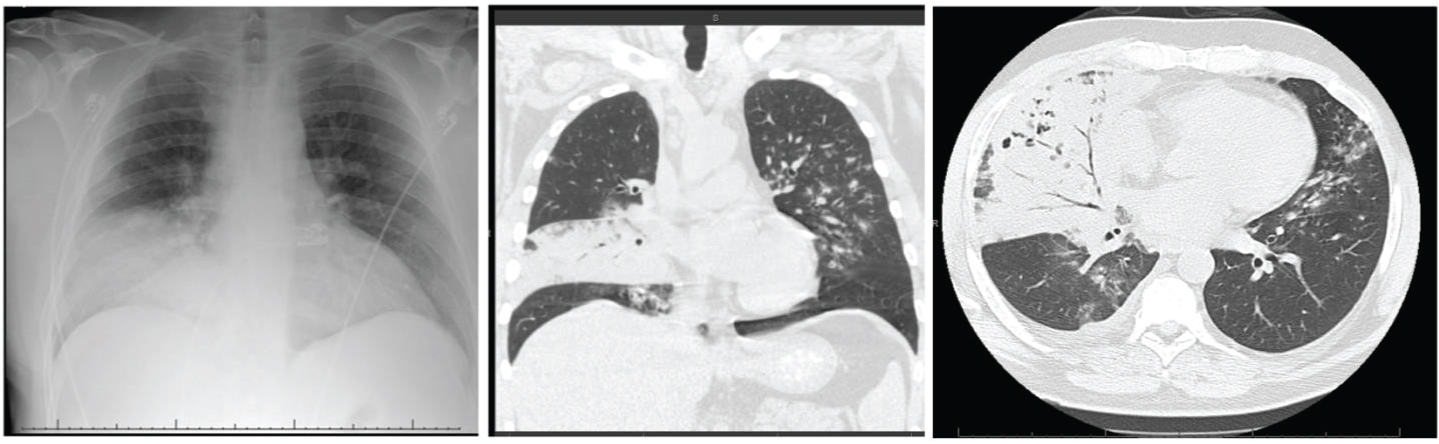

She was admitted to intensive care unit (ICU) with diagnosis of septic shock and diabetic ketoacidosis (DKA). She was treated with broad spectrum antibiotics, vasopressors, fluid resuscitation, multiple blood transfusions, and insulin drip and started to improve clinically. She was subsequently found to have elevated total bilirubin of 4.6 mg/dl (n = 0.2-1.1 mg/dl), which was most likely due to cyclosporine [6]. However, magnetic resonance cholangiopancreatography (MRCP) was done to investigate hyperbilirubinemia which showed hepatic hemosiderosis and left sided pleural effusion concerning for empyema. Pleural effusion (as shown in Figure 1A) was drained along with chest tube placement (Figure 1B) and fluid analysis of pleural effusion confirmed diagnosis of hemothorax, which was most likely to be spontaneous in setting of low platelet count. Patient was requiring almost daily platelets and packed red blood cells (PRBC) transfusions. Computerized tomography (CT) scan of chest was performed after thoracentesis and was suggestive of decreased left sided pleural effusion and four nodular opacities in right upper and lower lobes (as shown in Figure 1C and Figure 1D).

Figure 1: A) Chest X-ray (CXR) shows left sided pleural effusion; B) CXR post left sided chest tube placement; C) Computerized tomography (CT) chest showing right medial upper lobe nodule; D) CT chest showing right subpleural based nodule. View Figure 1